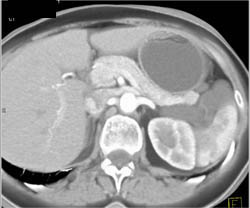

Lymphangioma